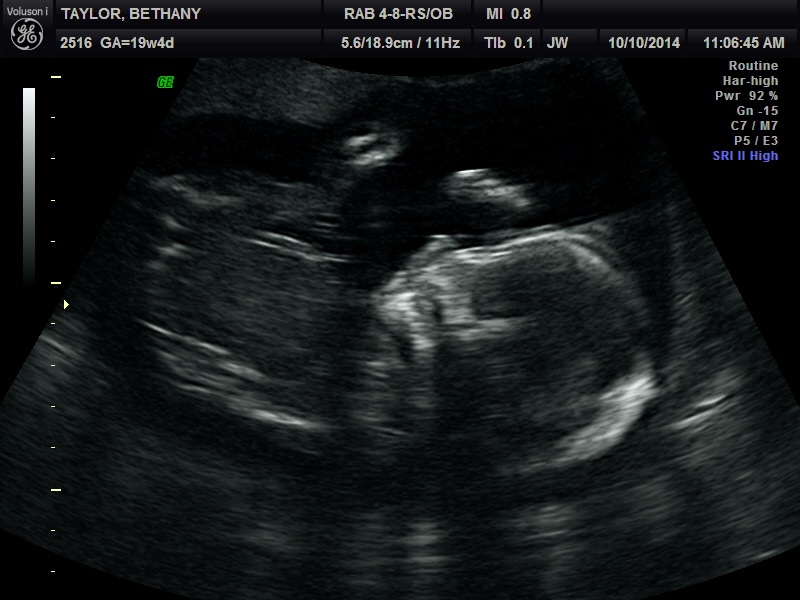

Baby!!

What? You thought we were going to tell you the sex of our unborn baby? Sorry kids, you thought wrong. We can’t tell you because we don’t know. This time around we’re not finding out.